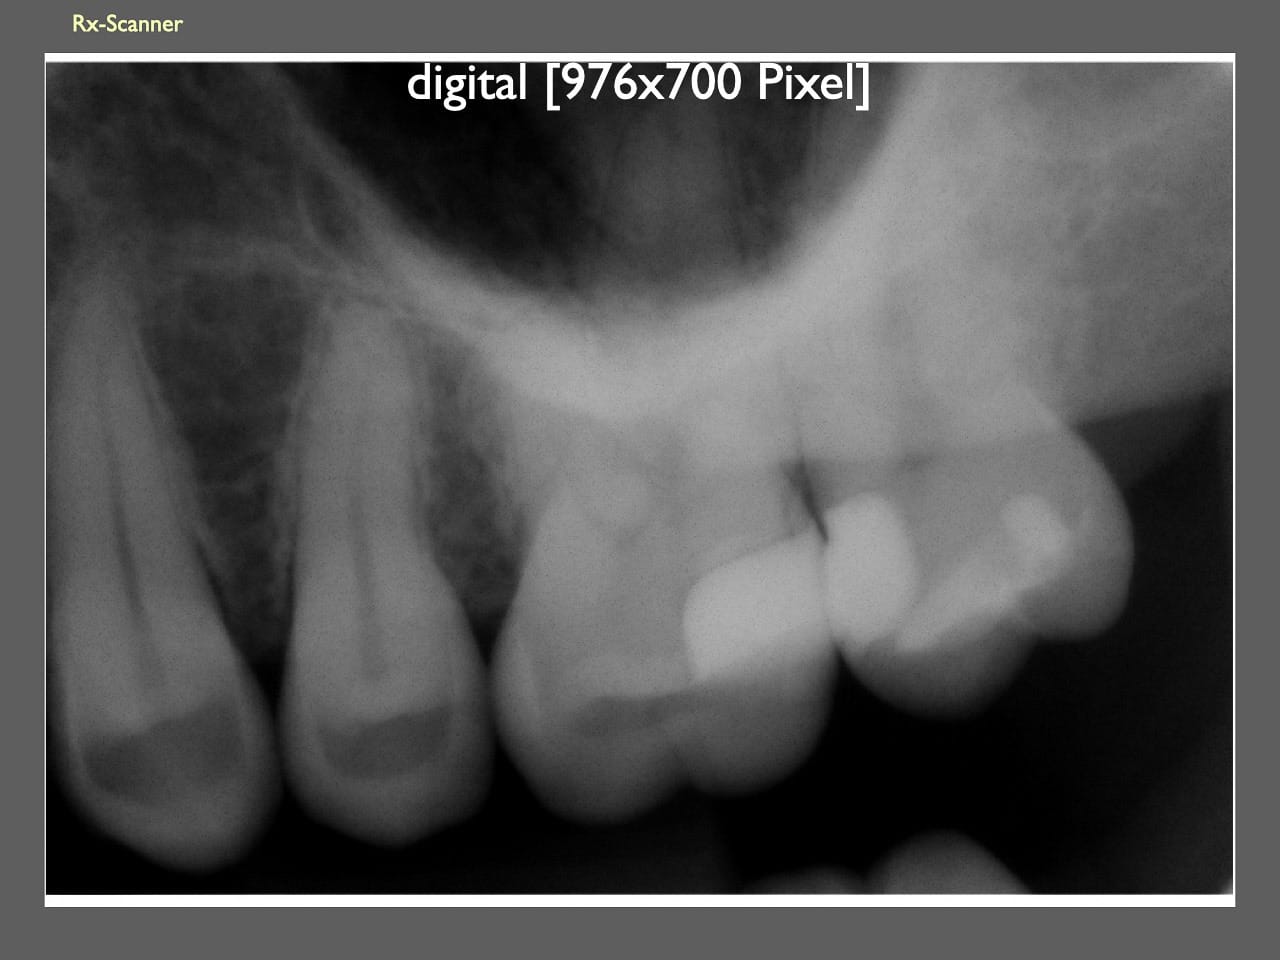

dental Scannen in der Zahnarztpraxis. Study Club vom 28.2.2010. Von peter portmann, Veröffentlicht am 28. Feb. 2010 — 3 min Lesezeit dokumentationfoto Auf dieser Seite Zahnarztpraxis-Trilogie zu Fotografie und Dokumentation Portrait Fotografie Scannen Scannen